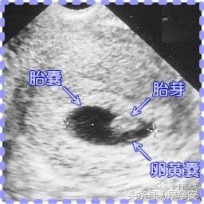

胎芽是什么?在受精卵发育过程中,最初两周称为孕卵,以后各器官逐渐形成,经历孕囊—胎芽—胎心,最终形成胎儿。

在精子和卵子结合形成受精卵以后,着床受精卵慢慢的分裂成多细胞的孕囊,在怀孕三十多天以后,各原始细胞进行分化,慢慢形成胎芽,胎芽进一步发展形成胎心。这就是一个胎儿形成的过程。

因为胚胎的发育,30—40天形成的是胎囊,40—50天形成的是胎芽,50—60天形成胎心,所以一般的做B超应该是在60天左右的时候做,这时就能够看到胎囊、胎芽、胎心是否正常。